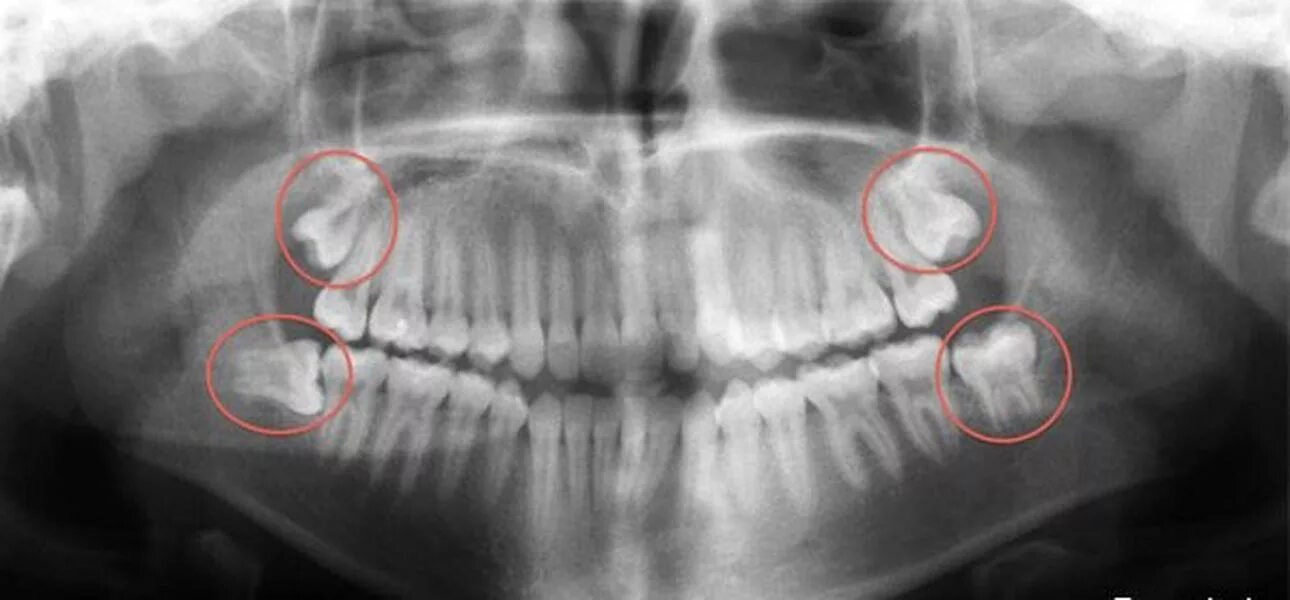

Снимок верхней и нижней челюсти